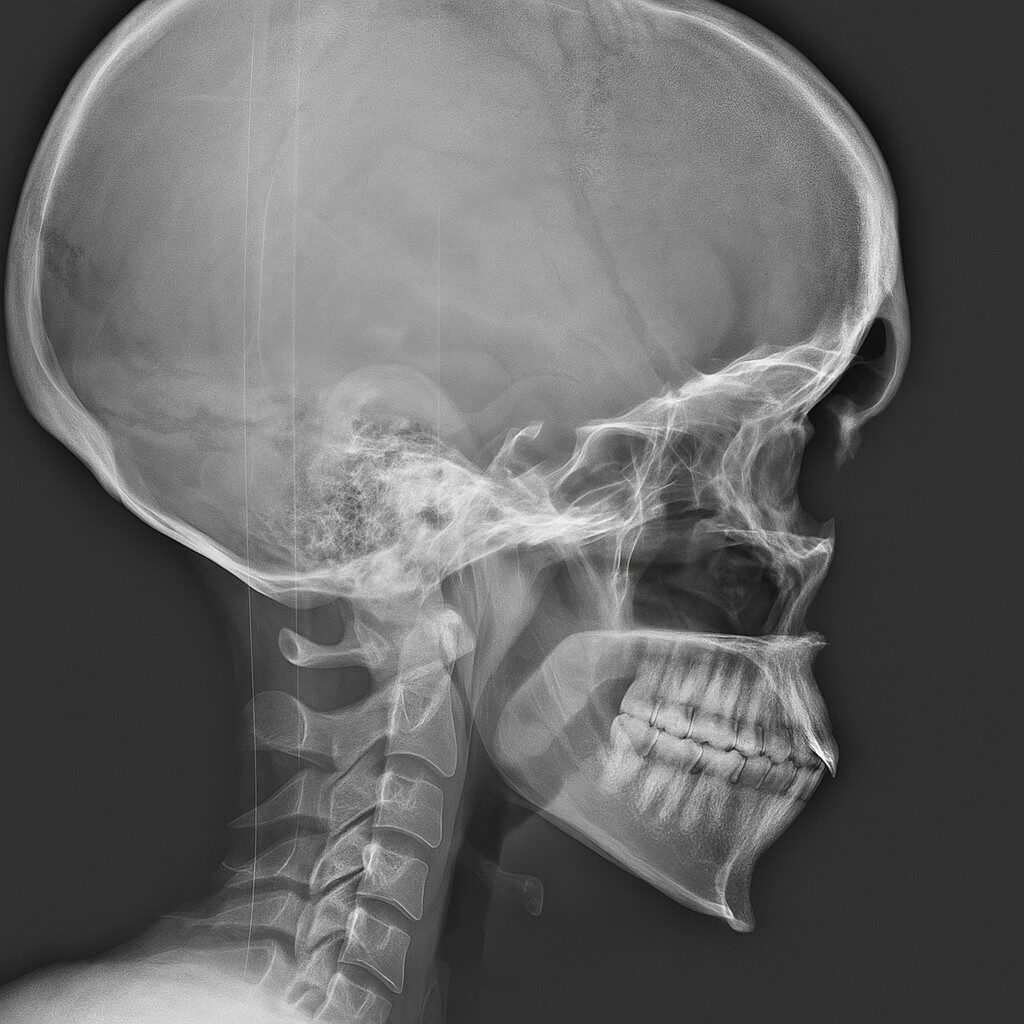

Indikationen zum Schädelröntgen ?

Das Schädelröntgen gehört zu den ältesten bildgebenden Verfahren in der Radiologie. Während CT und MRT heute die Standardverfahren für die […]